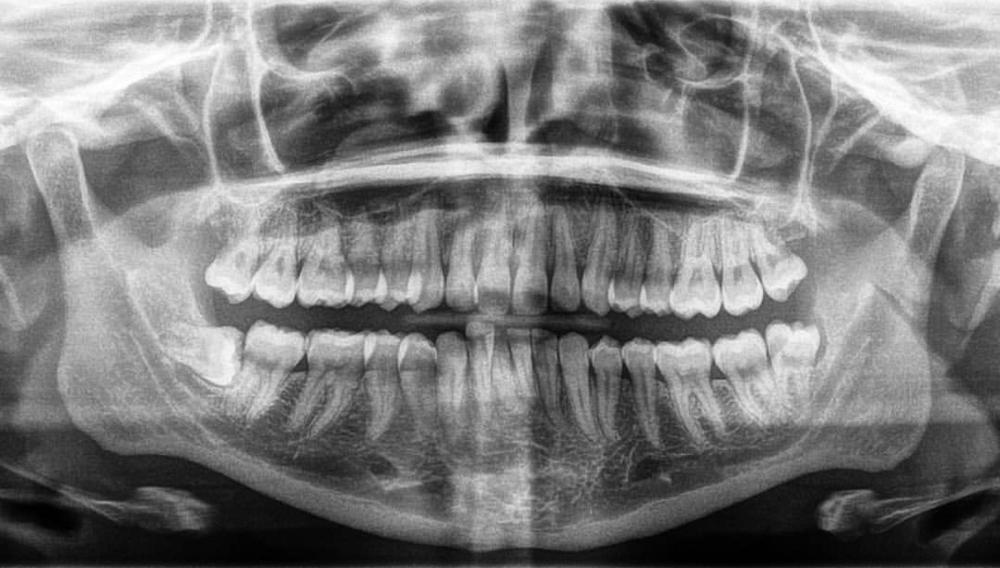

Below are examples of a few sets of surgeries that we routinely perform: